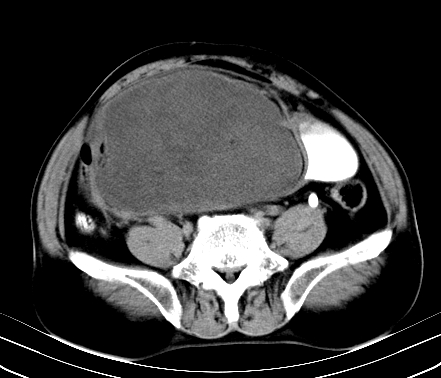

标题: CT19729B:男,74岁,因腿疼就诊,查体触腹部肿物,

增强扫描

动脉期

【ct表现】

1、肿块巨大,往往位于腹膜后,长大后才引起症状而就诊;那么位于腹膜后的肿瘤80%为恶性肿瘤。

2、实性肿瘤,增强扫描轻度不均强化,实性肿瘤一般不是好东西。

3、肿瘤边缘似见少许脂肪样密度。

4、腹膜后未见肿大淋巴结,但肿瘤于临近的肠管及组织接触紧密。

【诊断】

腹部占位,考虑位于腹膜后的恶性肿瘤,脂肪肉瘤(实体型)可能性大。

术后病理结果:腹膜后脂肪肉瘤。